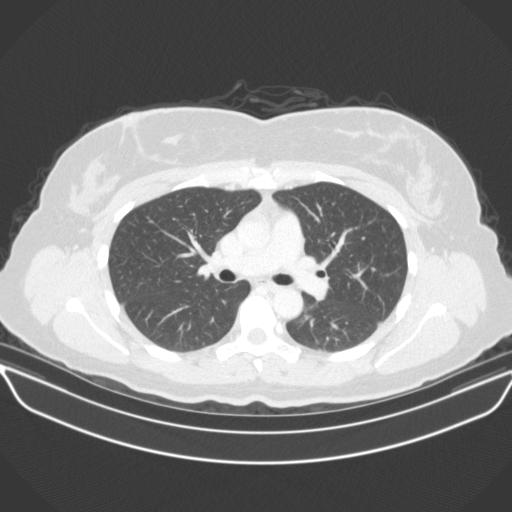

Reconstructed NATIVE CT scan (cycle consistency)

Full window (WL 1023.5, WW 4095 β†’ Low βˆ’1024, High +3071)

Lung window (WL -600, WW 1500 β†’ Low βˆ’1350, High +150)

Mediastinum window (WL 40, WW 400 β†’ Low βˆ’160, High +240)